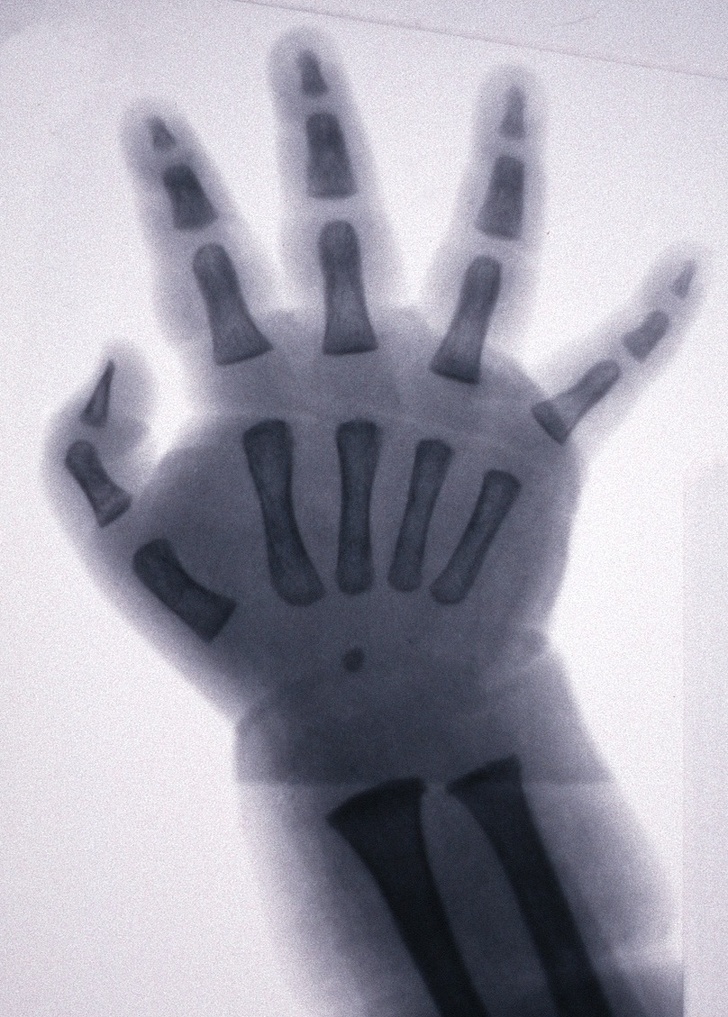

4. Рентгенівський знімок людини з полидактилией